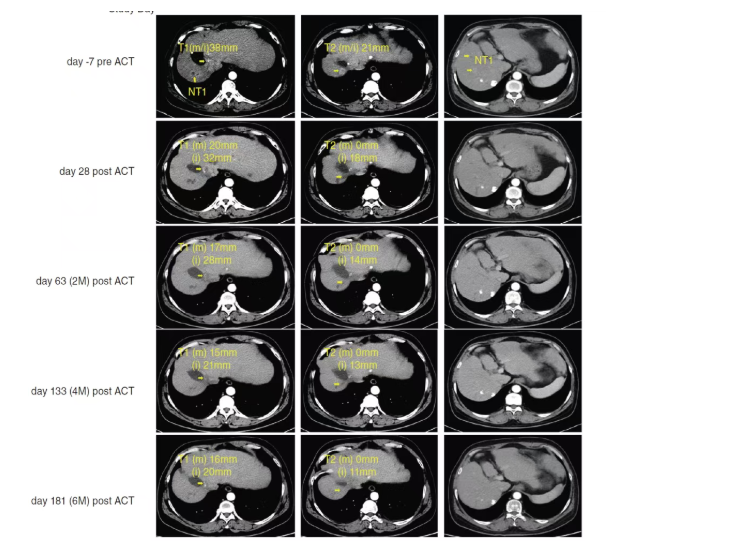

03 临床成果惊人:28天肿瘤显著缩小,病毒量大幅下降

这项突破性研究针对一名54岁晚期乙肝相关肝癌患者。该患者既往接受过手术、介入治疗、靶向药等多种治疗,但病情仍未有效控制。

在接受单次SCG101输注后,观察到了令人振奋的结果:

1. 肿瘤显著缩小

• 治疗前:右肝两个靶病灶直径分别为38mm、21mm

• 治疗后28天:肿瘤大面积坏死,目标病灶缩小74.5%

• 持续有效:病情稳定保持6.9个月以上